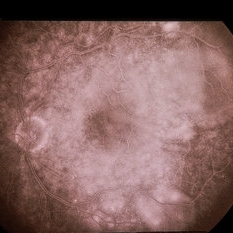

Color photograph of normal fundus.

Condition/keywords: normal eye, normal retina